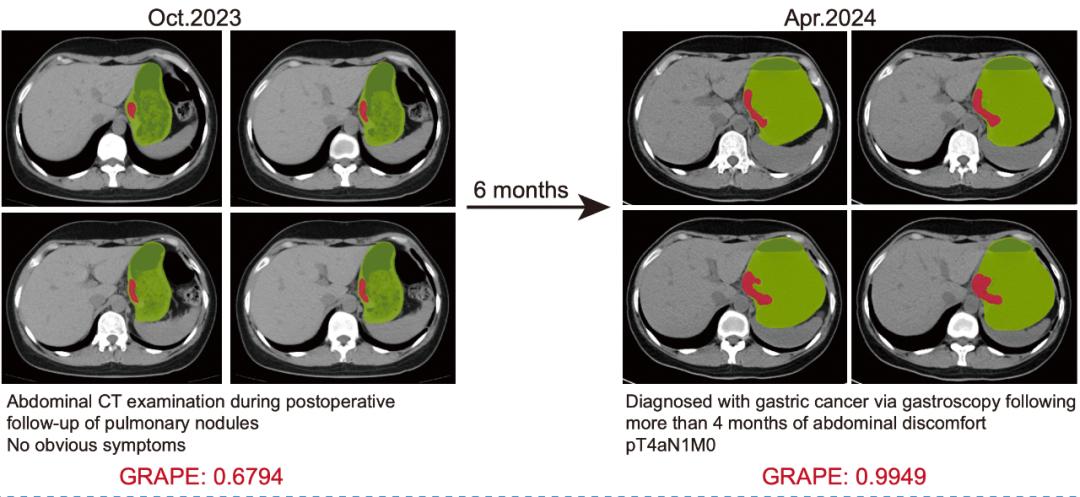

浙江省肿瘤医院胃外科医生胡灿提到,2024年4月,一名患者检测出局部晚期胃癌。医生回溯研究时,将6个月前检查某些疾病的CT图像喂给DAMO。 GRAPE,提醒他们有早期的胃癌疾病。

如果当时有AI自动检测,这个病人会提前6个月确诊并接受治疗。

在这项研究中,共回顾了11名病人确诊前的CT影像,发现AI可以提前2-10个月检测出胃癌。